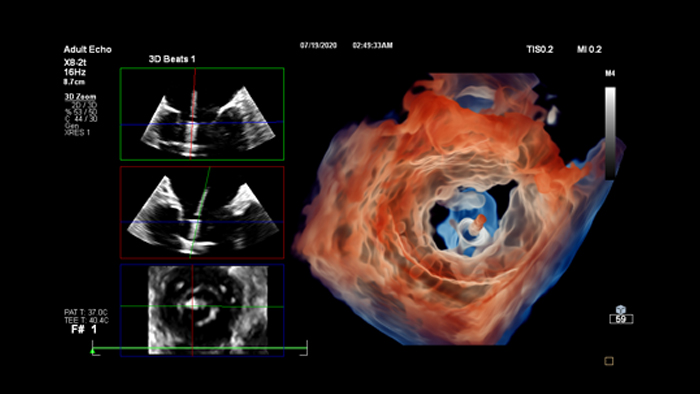

• Echocardiography: fast, accurate, reproducible advanced quantification tools in the echo lab with seamless workflow from scanning to reading room.

Ultrasound workflows

Ultrasound Workspace

​Allow for greater efficiency in viewing, analysis and reporting by giving care teams the flexibility to adopt different workflows based on their current and future needs.​

Cardiac Ultrasound

Enhance diagnosis confidence and clinical efficiency through superior image quality, advanced quantification tool and automation technology.